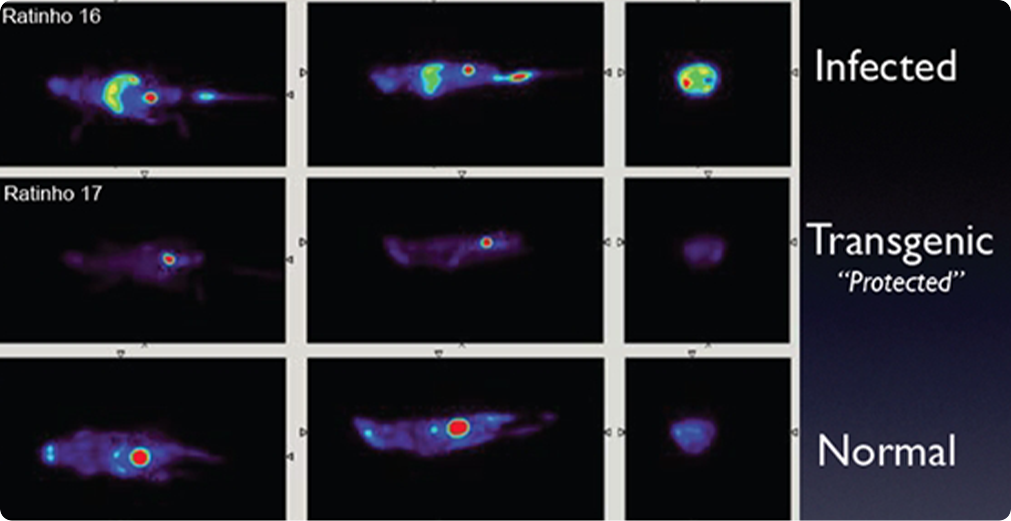

Due to its very good spatial resolution and accessibility of the Field-of-View, the Clear-PEM system can also be used for small animal imaging.